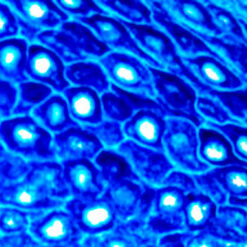

The PTAH Stain Kit is intended for use in the histological visualization of collagen, striated muscle, glial fibers and collagen without using Zenker’s Fixative containing Mercuric Chloride. This kit may be used on formalin-fixed, paraffin-embedded or frozen sections.